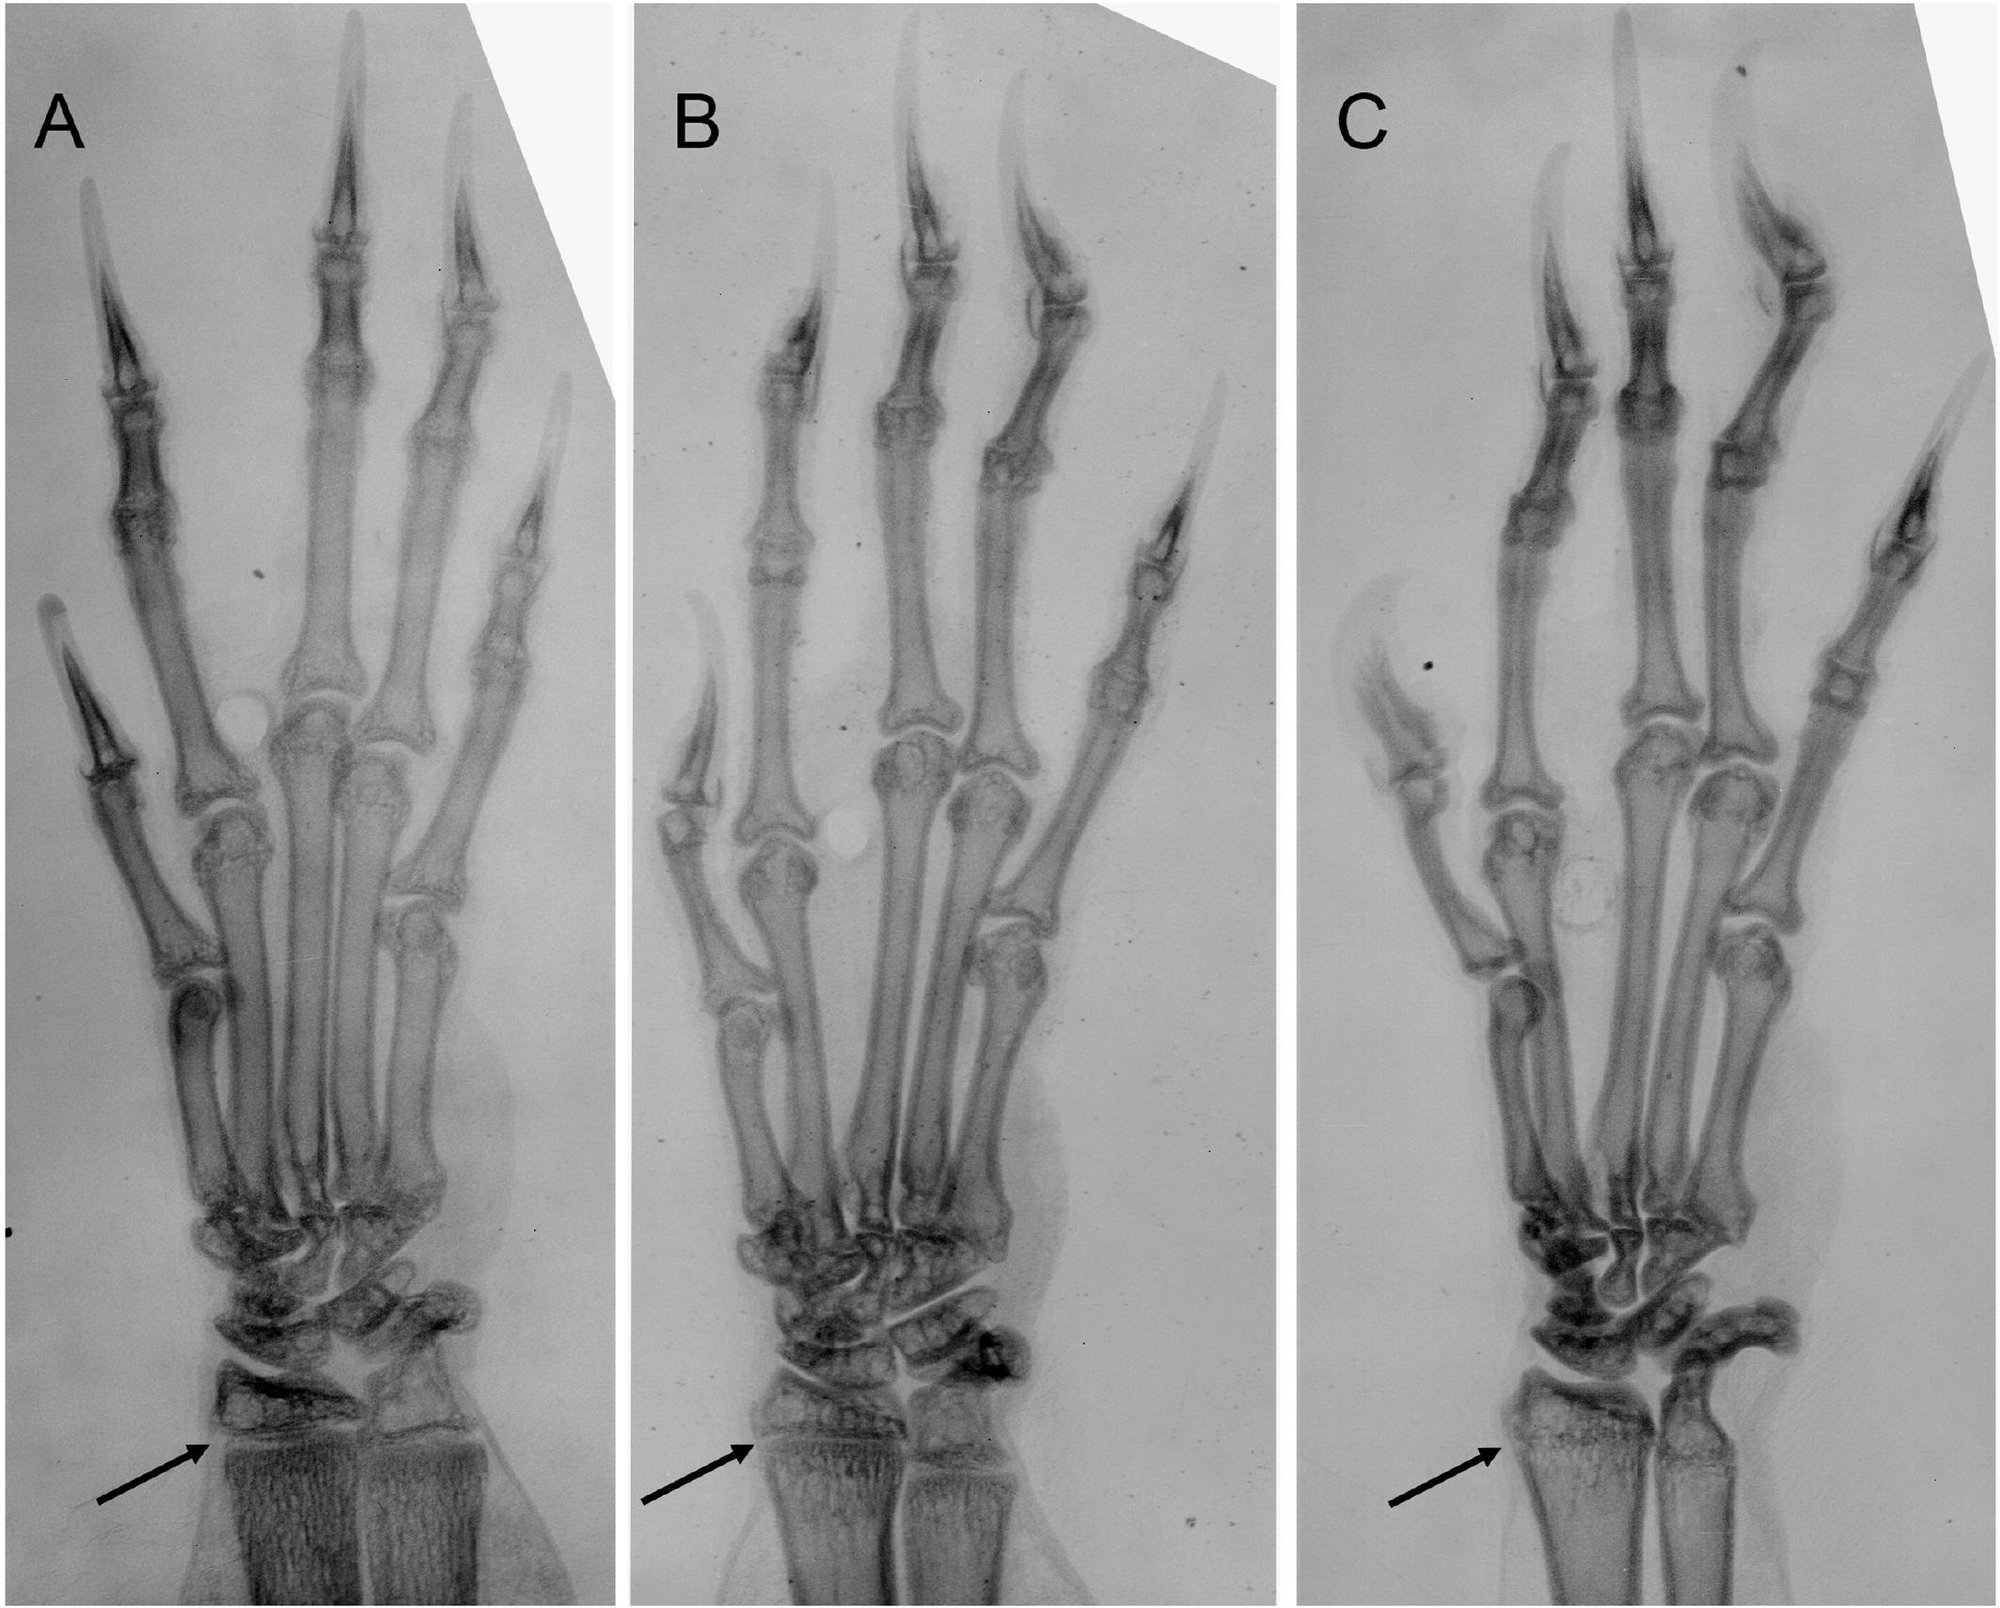

Hành trình chọn lọc tự nhiên vĩ đại trang bị cho bàn tay con người ngày nay 27 xương riêng lẻ, tương ứng với chúng là 27 khớp, 34 bó cơ và 123 dây chằng. Điều này biến bàn tay bạn trở thành nơi có mật độ xương, khớp cao nhất cơ thể.

Chỉ với thể tích bằng 1,5%, hai bàn tay chứa tới 15% tổng số lượng khớp và 25% tổng số lượng xương trên người bạn.

Chưa kể, hầu hết các xương và khớp trên bàn tay của con người có phạm vi chuyển động lớn và cực kỳ chính xác. Đó là điều tạo nên sự khác biệt. Bởi cũng với 26 xương, 33 khớp, 19 cơ và 57 dây chằng, bàn chân của bạn lúc này đang không làm được gì hơn việc ngọ nguậy dưới gầm bàn.

Điều đó nói lên rằng chính thiết bị hiệu ứng cuối cũng cần mở rộng bậc tự do của chúng. Con người, đang sở hữu một End effector với 27 bậc tự do gắn trên cánh tay của mình. Đó chính là những bàn tay với 27 khớp xương chuyển động linh hoạt.

Đến đây, có thể nói rằng một thế giới mà chúng ta đang thiết kế phù hợp với bàn tay chính là thế giới có UX/UI phù hợp với 27 bậc tự do mà bàn tay chúng ta sở hữu.

Trở lại với Dactyl, bàn tay máy mà OpenAI đang huấn luyện tại trụ sở của họ ở San Francisco. Nó mới chỉ đạt tới được 20/27 bậc tự do so với bàn tay con người. Con số thấp hơn 2 bậc so với MPL v2.0, bàn tay do Phòng thí nghiệm Vật lý Ứng dụng Đại học Johns Hopkins chế tạo.

Với một khoản tài trợ lên tới 120 triệu USD từ Cơ quan Chỉ đạo các Dự án Nghiên cứu Quốc phòng Tiên tiến Hoa Kỳ (DARPA), MPL v2.0 đã đạt được 22/27 bậc tự do so với bàn tay người.

Kỷ lục bàn tay máy với bậc tự do gần với bàn tay người thật nhất đang được nắm giữ bởi Clone Robotics, một công ty chế tạo robot của Ba Lan. Tháng trước, họ vừa giới thiệu một bàn tay robot được làm từ sợi carbon với cấu trúc giải phẫu giống với bàn tay người thật nhất từ trước đến nay.

Bàn tay được gọi là Clone Synthetic Hand v18 cấu tạo từ 27 khớp và 37 bó cơ. Điều này cho phép nó đạt được toàn bộ 27 bậc chuyển động tự do của bàn tay người bao gồm: ngón tay cái xoay tự do, các ngón tay co gập, chuyển động trái phải, cổ tay xoay được, tái tạo tư thế sấp và ngửa của cẳng tay, khóa khớp khuỷu tay…